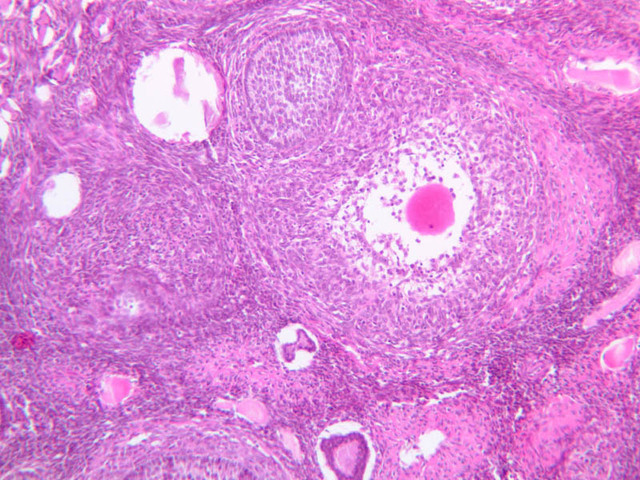

Secretory Phase

This phase occurs on days 15 to 27 and corresponds to the ovarian luteal phase characterized by rising levels of progesterone. The epithelial cells begin to secrete a mucoid fluid rich in nutrients, especially glycogen. The glands become highly coiled and folded and toward the end, very distended. The density of the stroma lessens as it becomes edematous. (slides B-99 [2.5x, 10x, 20x, 40x] [2.5x, 10x, 20x, 40x]; B-100 [1x, 2.5x] [2.5x, 10x, 20x, 40x] [2.5x, 10x, 20x, 40x])